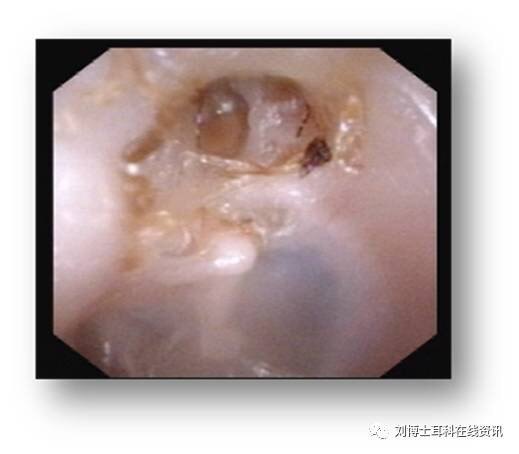

鼓膜又稱耳膜,屬于中耳的一部分,是橢圓形半透明狀薄膜,大小約9*8mm,由上皮層、纖維層和黏膜層構(gòu)成。 鼓膜穿孔是門診常見的疾病,可導(dǎo)致聽力下降和中耳反復(fù)感染。鼓膜穿孔不能自愈的話常常需要修補(bǔ),鼓膜修補(bǔ)術(shù)是耳顯微外科最基本的手術(shù)。 鼓膜穿孔根據(jù)部位分為緊張部穿孔和松弛部穿孔,根據(jù)穿孔大小又分為大、中、小穿孔。 鼓膜穿孔的原因 為了避免發(fā)生鼓膜穿孔,我們首先得了解鼓膜穿孔的原因。鼓膜穿孔最常見的原因包括:各種急慢性中耳炎、外耳道膽脂瘤、中耳膽脂瘤、鼓膜外傷、外耳道異物、腫瘤以及各種外耳道和鼓膜治療或操作繼發(fā)等。 1.急性中耳炎和慢性化膿性中耳炎 急性中耳炎和慢性化膿性中耳炎時由于炎癥、膿液的壓迫、腐蝕等原因?qū)е鹿哪ぞ植咳毖獕乃蓝鴮?dǎo)致鼓膜穿孔,急性期可看到鼓膜穿孔處有隨著脈搏的搏動,穿孔部位常常位于鼓膜緊張部。如感冒后耳痛則需要及時就診,排除中耳炎,早診斷早治療,避免加重導(dǎo)致鼓膜穿孔。中耳炎引起的鼓膜穿孔控制好炎癥,干耳后有一部分穿孔可以自愈,不能自愈的鼓膜穿孔需要行鼓膜修補(bǔ)手術(shù)。 2.外耳道膽脂瘤 外耳道膽脂瘤為外耳道皮膚脫屑、膽固醇結(jié)晶堆積、上皮包裹所形成的囊狀團(tuán)塊,其并非真性腫瘤,由于膽脂瘤呈膨脹性生長,周圍骨質(zhì)長時間受壓、破壞、吸收,向內(nèi)的擠壓或炎性反應(yīng)可導(dǎo)致鼓膜穿孔。當(dāng)外耳道堵塞、聽力下降、合并感染伴有耳痛,不易清理干凈時,排除了常見的“耵聹”栓塞外,就要考慮到有外耳道膽脂瘤的可能,再發(fā)現(xiàn)上皮樣碎皮和膽固醇結(jié)晶診斷基本明確診斷。有時還需要行顳骨CT檢查,以明確外耳道是否有骨質(zhì)破壞,鼓膜內(nèi)側(cè)的鼓室內(nèi)是否有累及。因此當(dāng)外耳道有堵塞時需要及時就診,以明確診斷。另外耳道分泌物或堵塞物多時,即使無明顯不適,也需定期復(fù)診。 3.中耳膽脂瘤 中耳膽脂瘤,尤其是后天原發(fā)的,常常會出現(xiàn)鼓膜松弛部內(nèi)陷、穿孔,松弛部會出現(xiàn)肉芽或膽脂瘤上皮,嚴(yán)重者可引起上鼓室外側(cè)壁及乳突的骨質(zhì)破壞。鼓膜松弛部穿孔是中耳膽脂瘤的一個特征性表現(xiàn),也是診斷的依據(jù)之一。中耳膽脂瘤具有破壞性,需要手術(shù)治療,清除病灶,保留或重建聽力。 4.鼓膜外傷 由于鼓膜很薄,所以在挖耳時易損傷鼓膜。鼓膜直接外傷,如銳性物(挖耳勺、火柴棍、牙簽、棉棒等)挖耳時可損傷鼓膜,化學(xué)腐蝕劑如硝酸銀、硫酸等、鋼渣、火花、熱油或開水等進(jìn)入耳內(nèi)接觸鼓膜均可導(dǎo)致鼓膜穿孔;爆炸或鞭炮的爆震波和氣流沖擊、掌擊傷(俗稱打耳光)、強(qiáng)烈水柱或氣流噴射、潛水、跳水時水壓過大等情況也可損傷鼓膜;頭顱外傷顳骨骨折也可損傷鼓膜;提高對上述損傷情況的防護(hù)很重要。 5.外耳道異物 外耳道異物分為生物和非生物兩大類。其中生物類有植物和動物類。非生物類的有球形、不規(guī)則的各種塑料品、小玩具、棉簽、火柴棍、紙團(tuán)、棉球、石子、沙土等。植物類:各種谷物、小果核、小豆類等。動物類:蚊蟲、蠅、蟑螂、水蛭、螞蟻和蜜蜂等。要看管好兒童或智障者勿將異物放入耳內(nèi);常見挖耳的習(xí)慣除了容易引起耳道感染也可有引起外耳道異物導(dǎo)致鼓膜損傷。另外,在夏季戶外活動應(yīng)注意防止各種蚊蟲和小生物進(jìn)入外耳道。 6.腫瘤 各種外耳道和中耳的腫瘤在生長過程中或合并感染均可引起鼓膜損傷導(dǎo)致穿孔。 7.各種治療或操作 分泌性中耳炎、外耳道異物、耵聹栓塞等疾病常常需要做各種治療或操作,如鼓膜穿刺、鼓膜切開和鼓膜置管等,這些操作本身就是對鼓膜的直接損傷,而咽鼓管吹張、外耳道沖洗、外耳道異物取出等治療都有鼓膜穿孔的風(fēng)險,中耳的各種手術(shù)如鼓室探查、鐙骨手術(shù)等也有鼓膜直接或繼發(fā)性損傷。